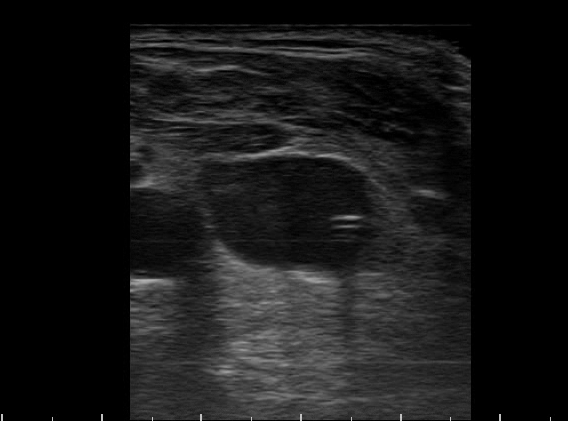

Post-procedure transverse view of the neck…what do you see?

…an internal jugular catheter in the jugular vein! Note the shadow behind it. In fact, the use of ultrasound to confirm venous position as well as eliminate pneumothorax often obviates the need for a post-procedural CXR, sparing time, resources, and the risk of turning/moving a critically ill patient (how many tubes and lines have been lost this way…).